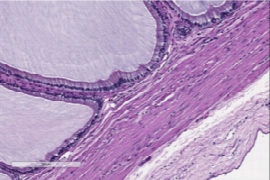

Dr. Le Roux graduated from the Veterinary School of Nantes, France, in 2006. After a rotating small animal internship in Toulouse and a radiology internship in Belgium, he completed a radiology residency program at the Veterinary School of Louisiana State University in 2013. Dr. Le Roux became a Diplomate of the European College of Veterinary Diagnostic Imaging in 2012, and a Diplomate of the American College of Veterinary Radiology in 2014. During his residency at LSU, he also started a Master of Science about histological and ultrasonographic correlation of small intestinal layering in dogs, that he completed in 2015. Dr. Le Roux has a special interest in gastrointestinal imaging in dogs and cats.